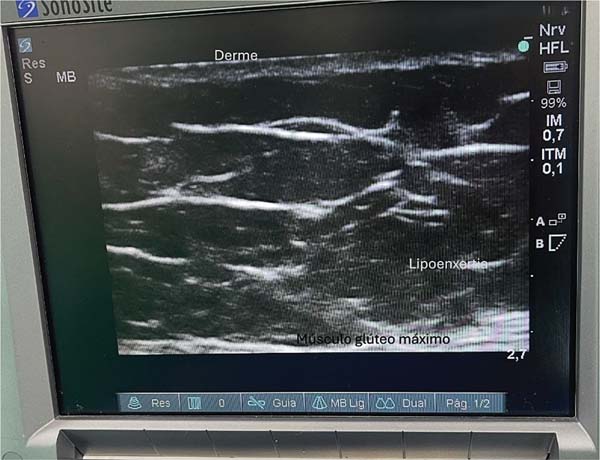

Classically, this region features two fascial layers and two fatcontaining subcutaneous tissue layers. The ultrasound evaluation reveals a thinner, more elastic fascial layer, as well as a thicker one. The thinner fascia divides the subcutaneous tissue into two layers, and fat deposition occurs in the space between them (►Fig. 1).

The anatomical structures of the gluteal region are visualized on a tenth-generation iPad (Apple Inc.) using Wi-Fi ultrasound. This examination enables the identification of the following layers: skin, dermis, superficial fat, superficial gluteal fascia (or Scarpa’s fascia), deep fat, and deep gluteal fascia. The latter lies just above the muscle, and it should be avoided at all costs. Ideally, fat grafting occurs in the deep fat layer. Preservation of the deep gluteal fascia, combined with incisions shorter than 1 cm, prevents fat migration into the muscle plane.9,10